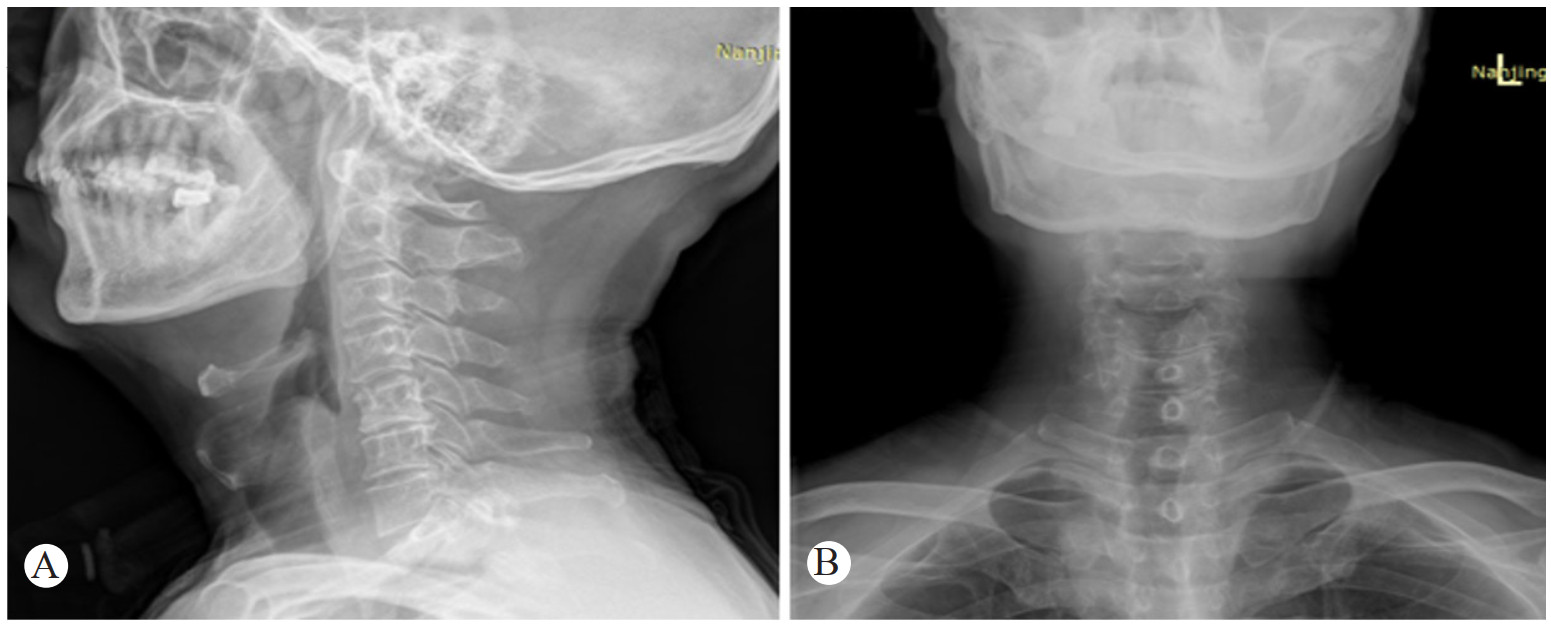

1 病例资料患者,男,58岁,因“咽痛9 h,加重伴胸闷1 h”急诊入院。患者于2020年4月1日下午13时出现咽痛、低热伴全身不适症状,咽部堵塞感。自服头孢拉定、牛黄上清片等药物咽痛症状无好转,18时因咽痛加重,吞咽时疼痛明显,曾尝试再次口服抗生素等药物,但由于吞咽困难持续存在,因此无法吞服。晚间患者咽部疼痛加剧伴流涎,无法忍受吞咽唾液,说话含糊不清,阵发性胸闷不适。遂于22:30至徐州医科大学附属宿迁医院急诊科就诊。急诊室进行体格检查:体温38.8 ℃,急性痛苦面容,扁桃体无明显肿大,咽后壁外观未见明显异常,颈部亦无明显肿胀的迹象,触诊无触痛,心肺听诊未见明显异常。急诊遂行颈、胸部CT及X线检查。颈部及胸部CT提示:会厌皱襞明显增厚伴喉室腔显著狭窄,慢支、肺气肿;颈部X线提示:会厌显著增厚,拇指征阳性(图 1、图 2)。急诊考虑“急性喉头水肿”遂予以急诊留观,给予甲强龙500 mg静脉滴注,同时予吸氧、监护等处理。鼻导管4 L/min时患者的外周血氧饱和度(SpO2)在95%左右。联系耳鼻喉科急诊会诊。

| 图 1 颈部正侧位片显示会厌显著增厚呈拇指征及塔尖征(黑色箭头) |

本例患者颈部X线提示会厌显著增厚,拇指征及塔尖征阳性(图 1),计算机断层扫描显示会厌皱襞明显增厚伴喉室腔显著狭窄(图 2)均提示病情危重,为临床干预提供可靠的依据。因此对于重症急性会厌炎的临床特点及危险性应有足够的认识,呼吸困难、流涎、喘鸣和坐直和呼吸困难重症急性会厌炎需要气道干预主要相关因素。本例患者因咽痛、吞咽困难、流涎、说话含糊不清等症状就诊,值班医生亦考虑到会厌炎可能,完善了CT及X线检查后很快出现严重的吸气性呼吸困难,躁动不安,血氧饱和度快速进行性下降,因患者黏痰较多,强迫半坐位无法平躺,在影像确诊后仅数分钟就因气道梗阻发展到心脏骤停。因此遇到在此类重症急性会厌炎患者,在诊治流程上如患者出现吞咽困难、流涎、喘鸣和呼吸困难,应考虑到为需要紧急气道干预患者,紧急送抢救室完善急诊喉镜评估,为建立人工气道缩短时间,避免检查及转运过程中因窒息导致的心搏呼吸骤停。